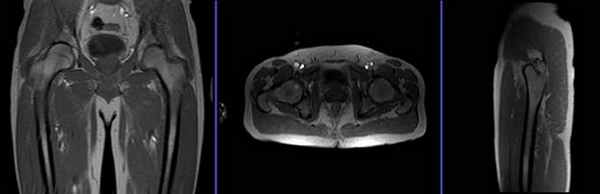

Первично при планировании последовательности должны быть выполнены снимки в 3 плоскостях. Выдержка снимков менее 25 сек, с получением Т1-взешенных изображений низкого разрешения.

Серия T2 stir, коронарный срез 3 мм до проведения атрографии

Планирование коронарных срезов на аксиальной плоскости; угловое расположение блока должно быть параллельно головкам правой и левой бедренных костей. Проверьте расположение блока на 2-х других плоскостях. Соответствующий угол должен быть получен в сагиттальной плоскости (параллельно бедру). Эти срезы должны полностью покрывать оба тазобедренных сустава, от уровня седалищных бугров до уровня лобкового симфиза.

Серия T1 турбо спин-эхо, аксиальный срез 3 мм, до проведения атрографии

Планирование аксиальных срезов на коронарной плоскости; угловое расположение блока параллельно головкам правой и левой бедренных костей. Проверьте расположение блока на 2-х других плоскостях. Соответствующий угол должен быть получен в сагиттальной плоскости (перпендикулярно бедру). Эти срезы должны полностью покрывать оба тазобедренных сустава, от уровня передневерхней подвздошной ости до малого вертела.